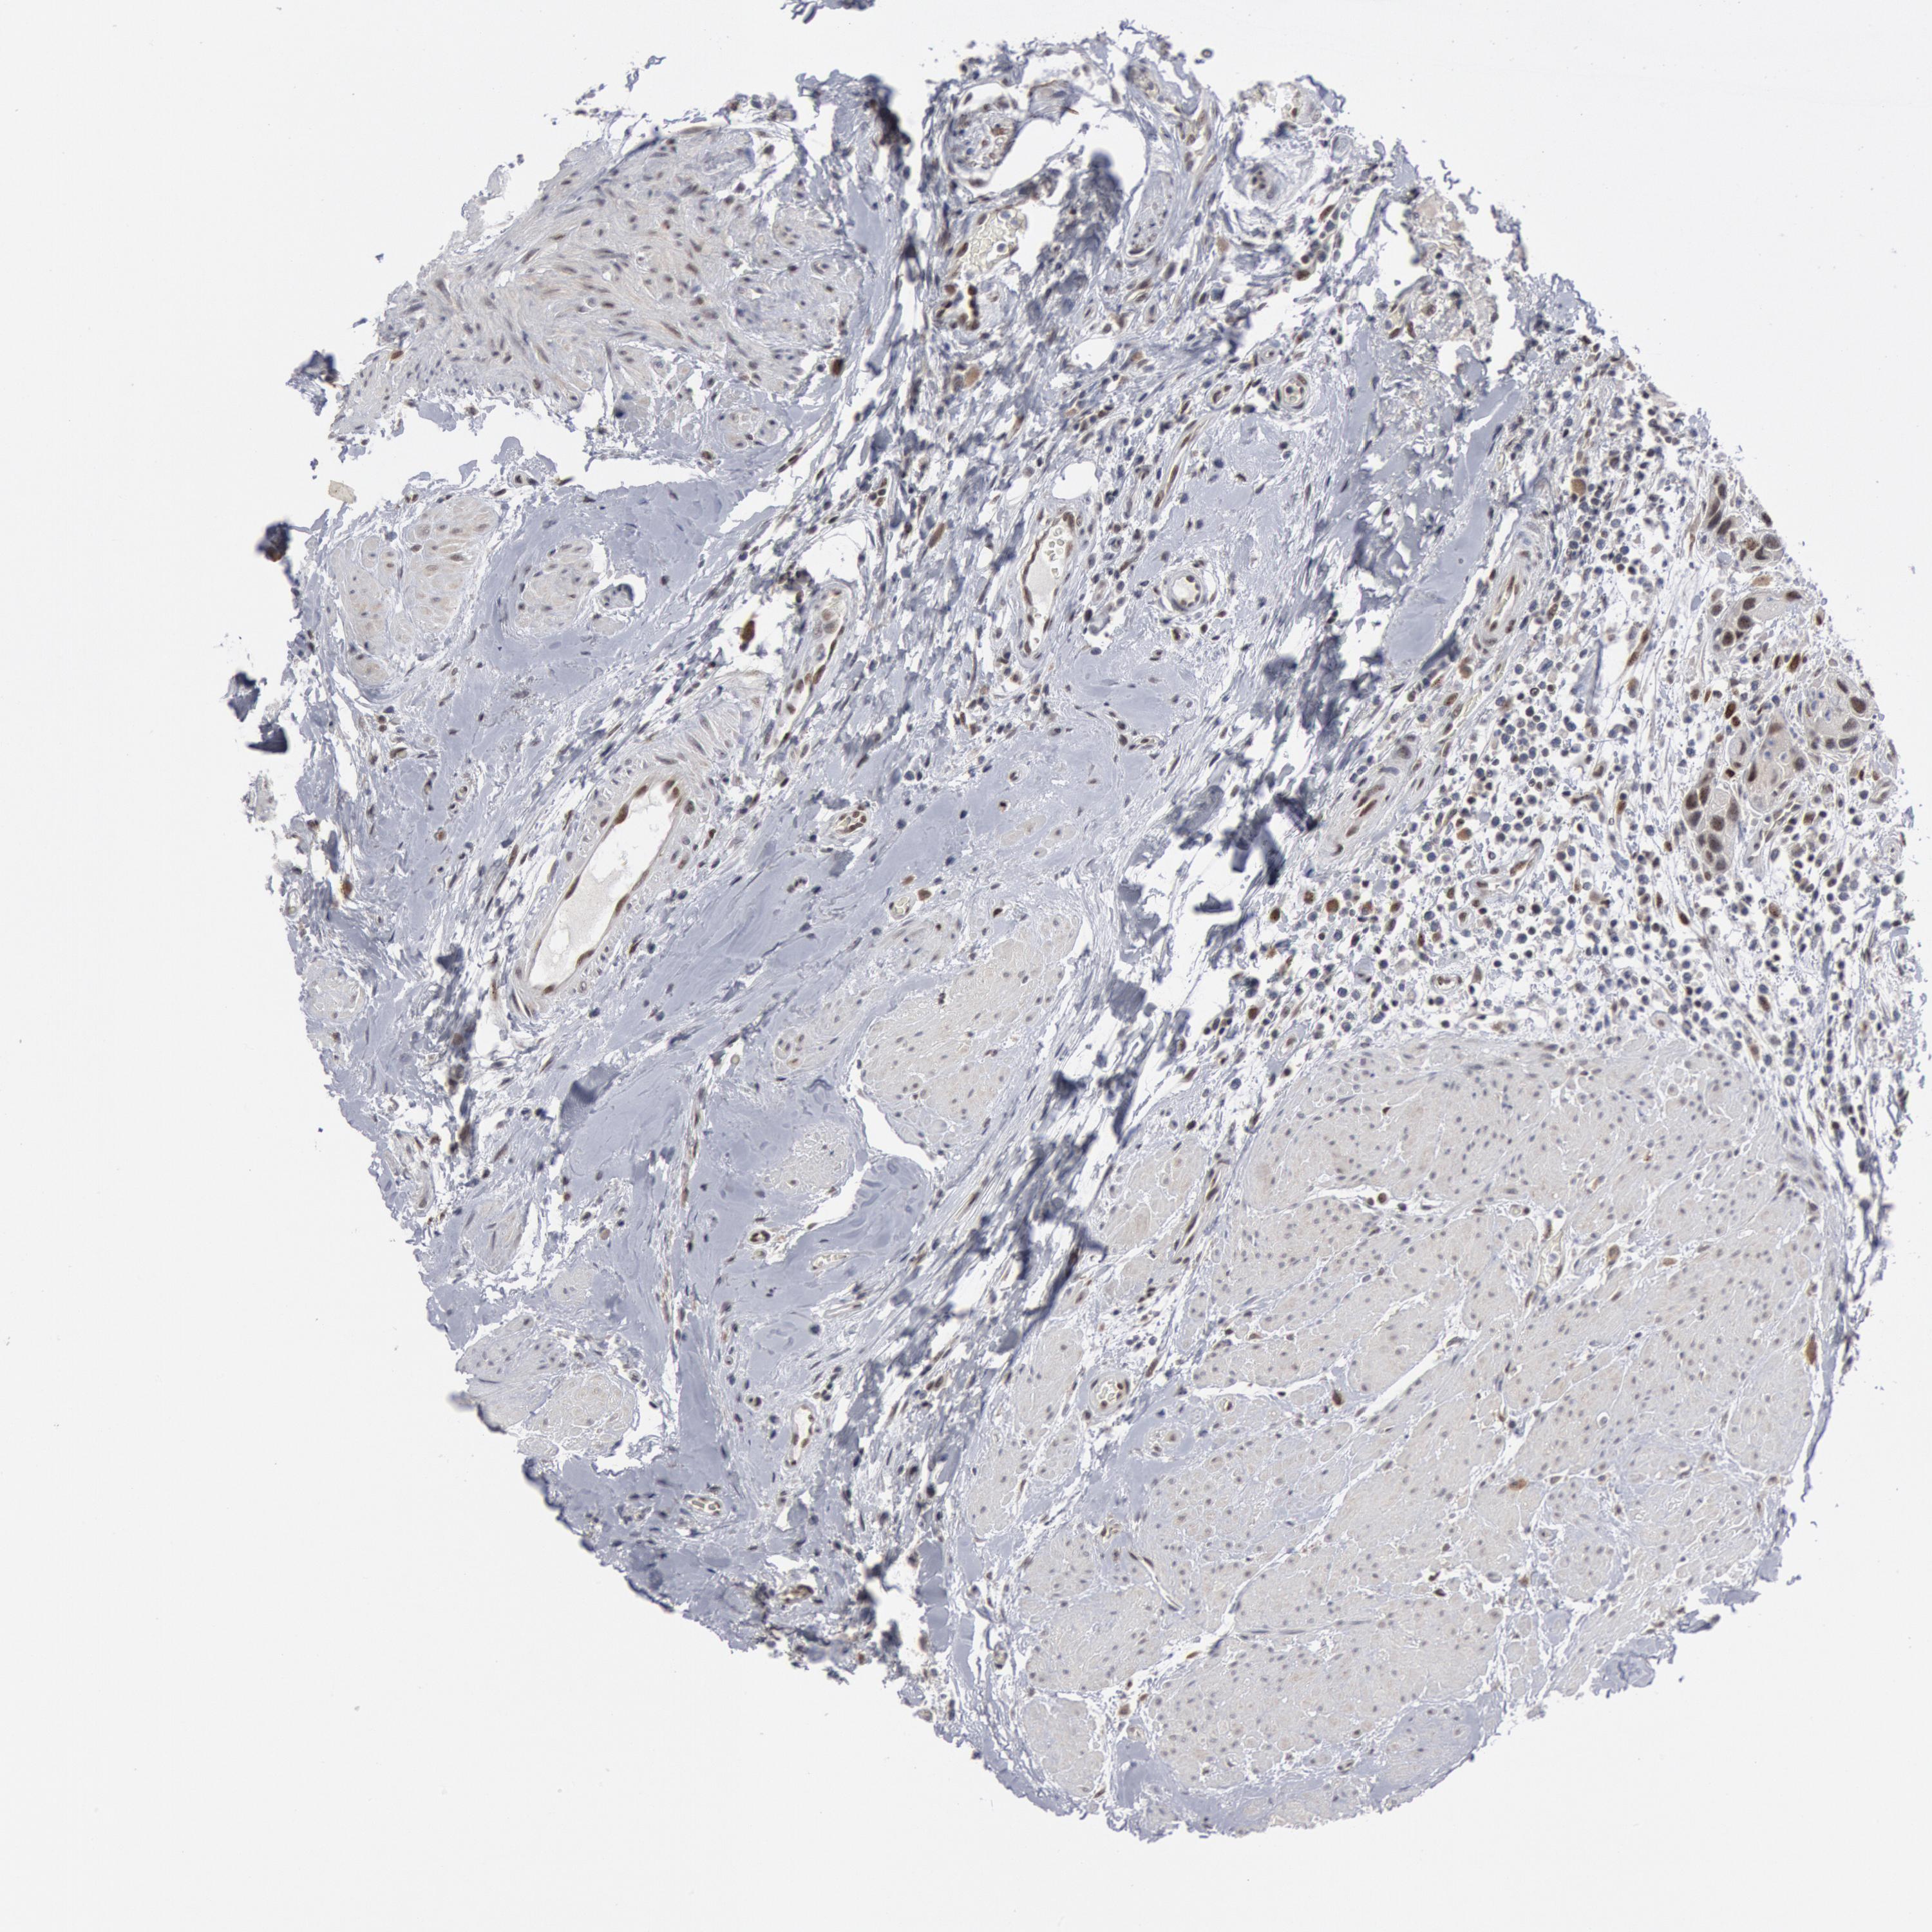

UROTHELIAL CANCER - Protein expressioni

A mouse-over function shows sample information and annotation data. Click on an image to view it in a full screen mode. Samples can be filtered based on level of antibody staining by selecting one or several of the following categories: high, medium, low and not detected. The assay and annotation is described here.

Note that samples used for immunohistochemistry by the Human Protein Atlas do not correspond to samples in the TCGA dataset.

Antibody stainingi

Antibody staining in the annotated cell types in the current human tissue is reported as not detected, low, medium, or high, based on conventional immunohistochemistry profiling in selected tissues. This score is based on the combination of the staining intensity and fraction of stained cells.

Each image is clickable and will lead to virtual microscopy that enables deeper exploration of all samples and also displays staining intensity scores, fraction scores and subcellular localization as well as patient and tissue information for each sample.

HPA001252

Urothelial carcinoma, High grade

Urothelial carcinoma, Low grade

Adenocarcinoma, NOS